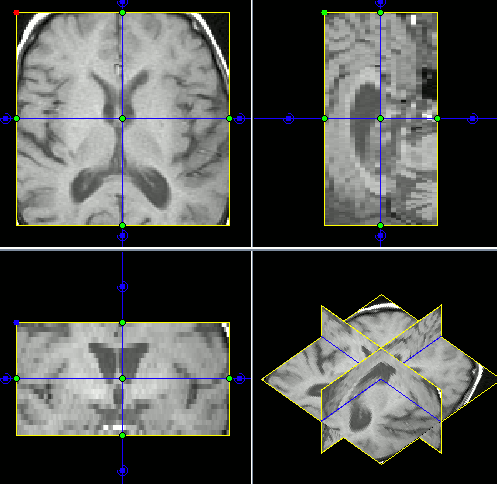

| 3.可視化と画像最適化 | DICOM、NIFTI、Analyze 7.5等、画像のリサンプリング、再配向、デモザイク、MPR 表示 | ![]() |

| 動画表示、3-D 可視化 | ||

| 直交表示 | ![]() |